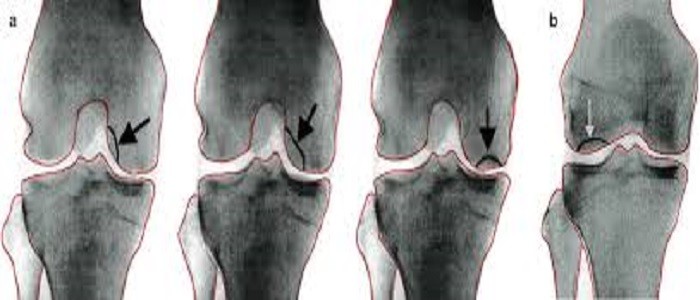

المرحلة الصفرية من خشونة الركبةحيث لا تظهر على الركبة أي علامات لوجود مشكلات بالركبة كما أن الألم في هذه المرحلة غير موجود ، وتسمى هذه المرحلة بالمرحلة الصفرية ونلاحظ عدم وجود علامات لتلف المفاصل .العلاج : لا يوجد علاج مطلوب لهذه المرحلة من خشونة الركبة .المرحلة 1 من خشونة الركبةستعاني الركبة في المرحلة الأولى من التآكل البسيط ومع ذلك ، في هذه المرحلة من غير المحتمل أن تشعر بالألم أو الانزعاج .العلاج:  لا يوصي أطباء العظام بأي علاج خاص للمرحلة 1 ومع ذلك ، قد يوصى بمكملات مثل الجلوكوزامين ، قد تكون التمارين المنتظمة مفيدة أيضًا بشكل خاصالمرحلة 2 من خشونة الركبةعلى الرغم من أن المسافة بين العظام تبدو طبيعية ، سيبدأ الأشخاص في الشعور بألم المفاصل عادة ، وستشعر المنطقة المحيطة بمفاصل الركبة بأنها متيبسة وغير مريحة ، خاصة عند الجلوس لفترة طويلة ، أو بعد النهوض في الصباح ، أو بعد التمرين ، على الرغم من أن الغضروف والأنسجة الرخوة لا تزال في حجم طبيعي ، إلا أن هناك تحللًا بروتينيًا للغضروف .العلاج:  هناك علاجات غير دوائية تعمل على تخفيف الألم الموجود في الركبة في هذه المرحلة ، ينصح العديد من المرضى بنظام صارم لممارسة الرياضة للعمل على تثبيت المفاصل بالإضافة إلى ذلك ، يمكن استخدام المشابك أو دعامات الركبة أو إدراج الأحذية لحماية الركبة من الإجهاد .المرحلة 3 من خشونة الركبةيشار إلى المرحلة 3 على أنها “معتدلة” ، حيث يوجد تآكل واضح لسطح الغضروف بين العظام والرجفان يضيق الفجوة بين العظام ، وهناك شظايا بروتيوغليكان وكولاجين تطلق في السائل الزليلي مع تقدم المرض ، حيث تتطور وتصبح الركبة أكثر خشونة .العلاج: يمكن وصف مضادات الالتهاب غير الستيروئيدية أو علاجات تخفيف الألم التي لا تستلزم وصفة طبية ، إذا لم تكن هذه الطرق فعالة ، فقد يصف طبيب العظام أدوية ألم أقوى ، مثل الكودايين والأوكسيكودون .قد يحتاج المرضى الذين لم يستجيبوا بشكل إيجابي للعلاج الطبيعي ، وبرنامج إنقاص الوزن ، واستخدام مضادات الالتهاب غير الستيروئيدية ، لزوجة التكميل ، وهي عبارة عن حقن داخل المفصل من حمض الهيالورونيك في مفصل الركبة ، يمكن علاج التهاب المفاصل المعتدل في الركبة بقوة من ثلاث إلى خمس حقن من حمض الهيالورونيك على مدار 3-5 أسابيع ، الأمر الذي قد يستغرق عدة أسابيع حتى يبدأ العلاج في إظهار النتائج ، ولكن عادة ما يستمر تخفيف الألم ستة أشهر .المرحلة 4 من خشونة الركبةتعتبر المرحلة 4 شديدة ، يتم تقليل مساحة المفصل بين العظام بشكل كبير ، مما يتسبب في تآكل الغضروف ، تاركًا المفصل صلبًا ، يؤدي انهيار الغضروف إلى استجابة التهابية مزمنة ، مع انخفاض السائل الزليلي الذي يسبب الاحتكاك وألمًا أكبر وعدم الراحة عند المشي أو تحريك المفصل .العلاج: العلاج هو إجراء جراحة العظام أو إعادة تنظيم العظام ، حيث يقوم جراح العظام بقص العظم أعلى أو أسفل الركبة لتقصير الطول والمساعدة في إعادة ضبطه من أجل تقليل الضغط على مفصل الركبة ، وتساعد هذه الجراحة على حماية الركبة عن طريق تحويل وزن الجسم بعيدًا عن موقع نمو حافز العظام وتلف العظام .خيار جراحي آخر هو استبدال الركبة استبدال كامل ، أو تقويم المفاصل خلال هذا الإجراء الجراحي ، تتم إزالة المفصل التالف واستبداله بجهاز تعويضات بلاستيكية أو معدنية قد يستغرق التعافي من الجراحة عدة أسابيع ويتطلب الصبر والانضباط ، مع العلاج البدني والمهني المستمر لاستعادة الحركة الكاملة .[2]